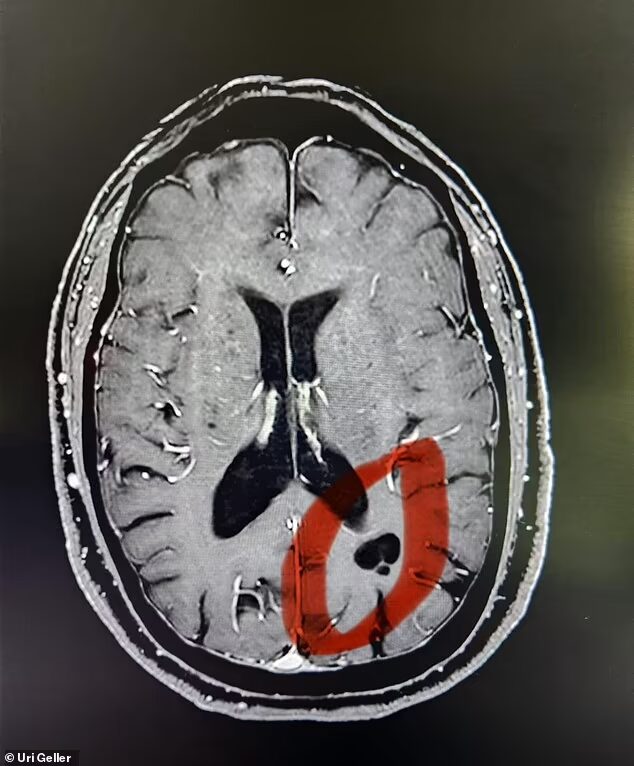

11月6日放映の「ノンストップ」(フジテレビ)は、10月27日付のイギリス紙『デイリー・メール』の報道を引用する形で、MRI検査の結果ユリ・ゲラーの超能力の秘密が明らかになったと紹介。MRI検査の結果、ユリ・ゲラーの脳に、普通の人にはない黒い影が発見された。ゲラー本人によればそれは宇宙人にインプラントされたもので、6歳の時遊んでいて、直径3メートルの球体から光線を額に浴びせられ、それから超能力を発揮し始めたという。川崎中央クリニックの市村真也院長によれば、この場所は後頭葉と頭頂葉の中間にあり、現代の技術ではこの場所に何かをインプラントすることは不可能だという。